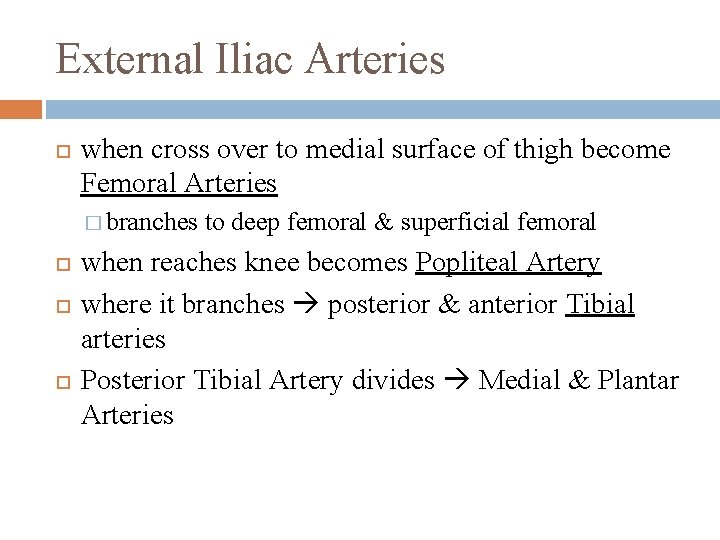

External Iliac Arteries when cross over to medial surface of thigh become Femoral Arteries � branches to deep femoral & superficial femoral when reaches knee becomes Popliteal Artery where it branches posterior & anterior Tibial arteries Posterior Tibial Artery divides Medial & Plantar Arteries